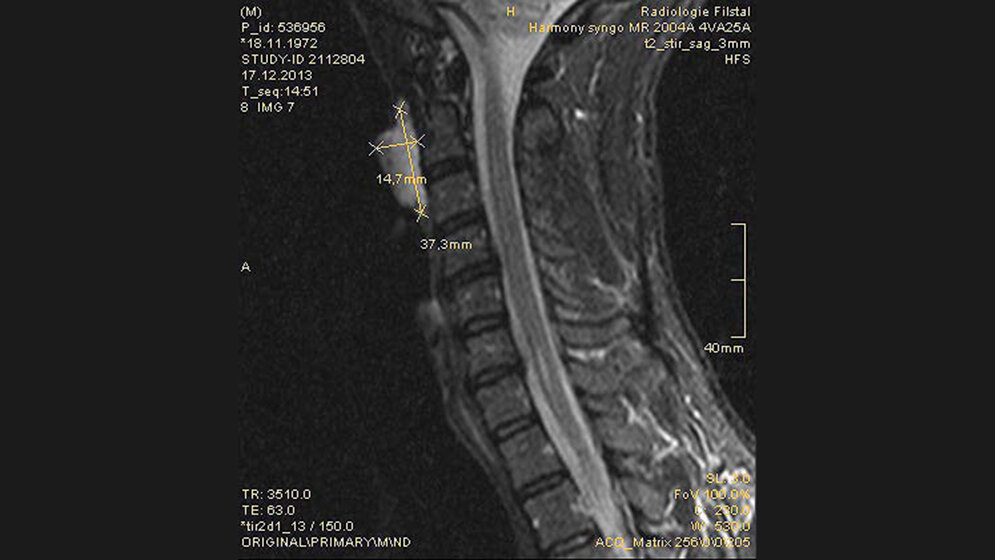

Zufallsbefunde: Thornwaldt-Zyste

Schnittbilddiagnostik der Wirbelsäule (7.18)

Die Thornwaldt-Zyste entsteht durch eine embryonale Fehlbildung des Notochords zum oberen Gastrointestinaltrakt. Die embryologische Situation und anatomische Lokalisation ist von der Rathke’schen Tasche im Bereich der vorderen Hypophysenregion zu differenzieren.